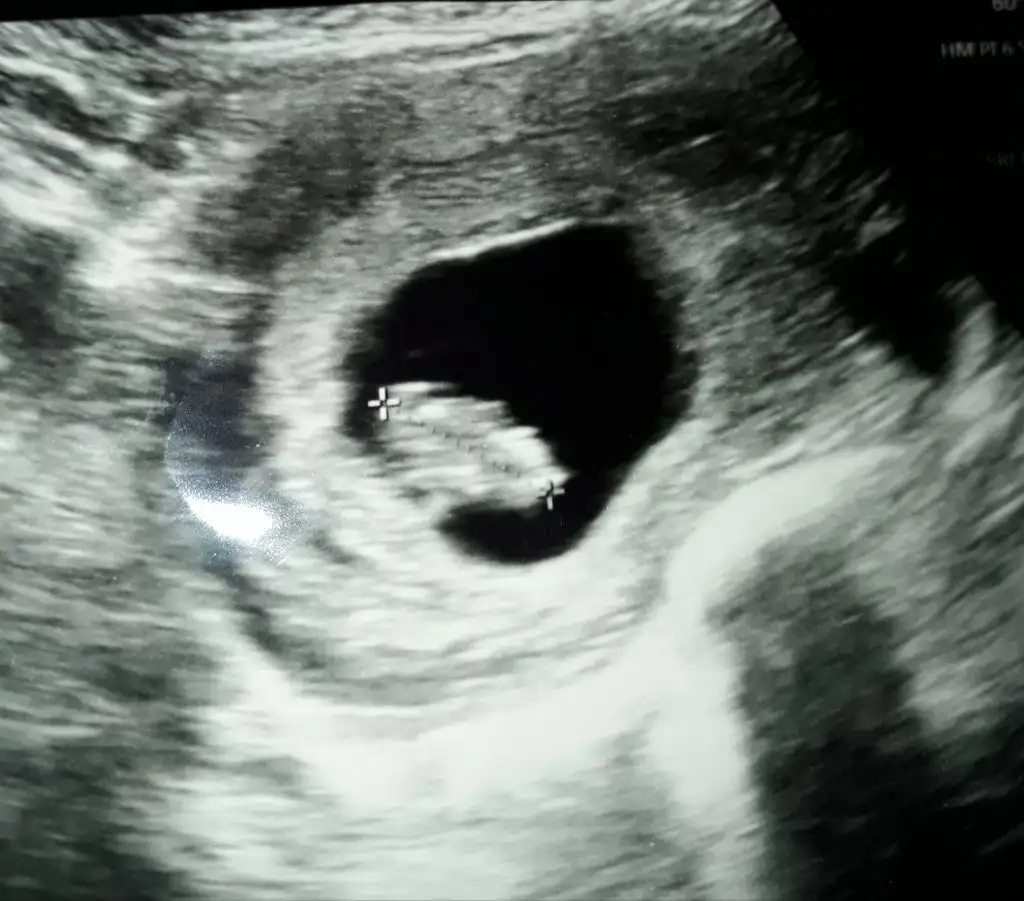

dr soylemeden siz gorun genital nub teorisi ( bebegin cinsiyeti)

Banada tahminde bulunabilir misinizzz🥰